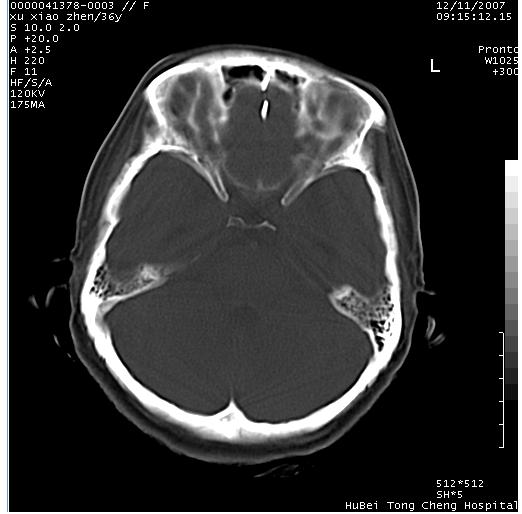

以下是引用wzr在2007-12-12 18:58:00的发言:[br]以脑白质受累,脑肿胀明显,脑室变窄,多考虑炎性改变,建议进一步ce或mri明确.

以下是引用wqs571018在2007-12-12 19:48:00的发言:[br]脑白质受累,脑肿胀明显,脑室变窄,多考虑炎性改变,脑膜炎可能性大;建议mri明确.。